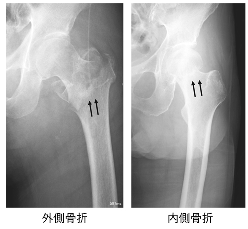

ビスホソホネート製剤やデノスマブという薬ですが、大腿骨骨折や圧迫骨折を予防する効果の高い良い薬です。

それに対して、「80歳以上の大腿骨骨折の患者さんは、1年後に5人に1人が亡くなっており、4人に1人が施設から自宅に帰れていない」そうで、骨折は命や生活の根本に関わる問題です。